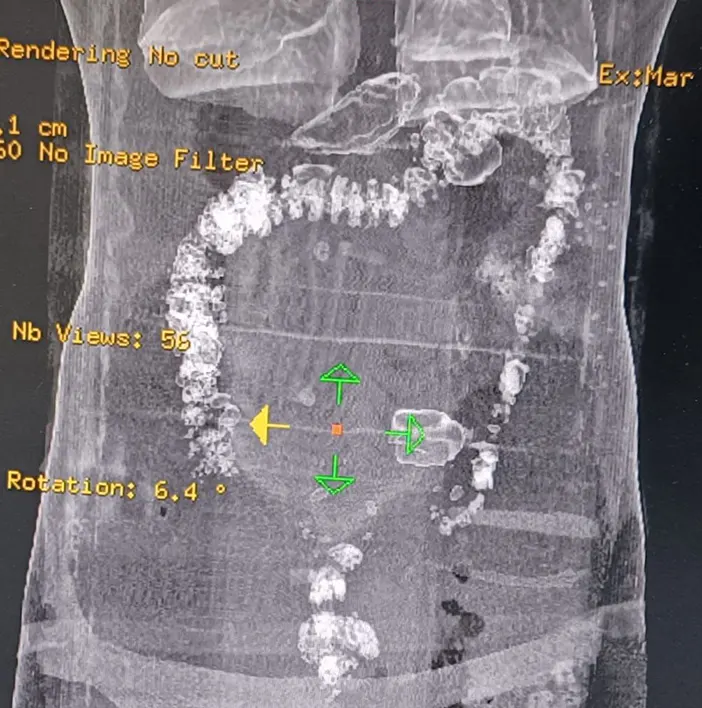

İran’dan Ağrı üzerinden Türkiye’ye giriş yapan İran uyruklu 4 kişi takibe alındı. İstanbul'a gitmek isterken Trabzon’da gözaltına alınan 4 kişinin durumundan şüphelenen ekipler, şahısların uyuşturucu madde yutmuş olabileceği ihtimali üzerine harekete geçti ve şahıslara röntgen çekildi.

Yapılan incelemede şahısların midelerinde kapsüller halinde yuttukları yaklaşık 2 kilo Metamfetamin olduğu tespit edildi.